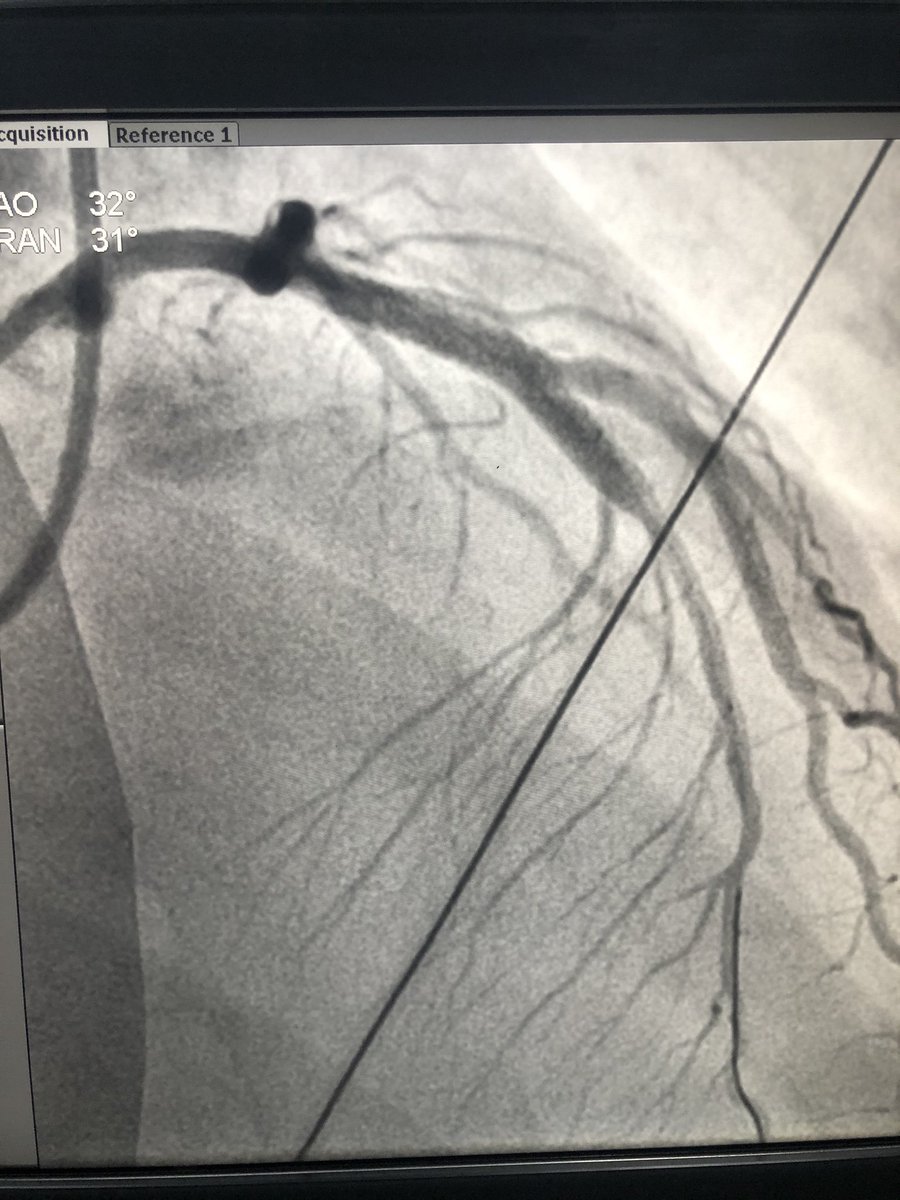

Thrombus aspirated .. Stented RCA

Aspirated and Stented LAD too .. didn't want to take a chance on LAD in this sick pt. By end of Plasty I could taper Dopa to 5mcg and Noradrenaline 0.5mcg ..